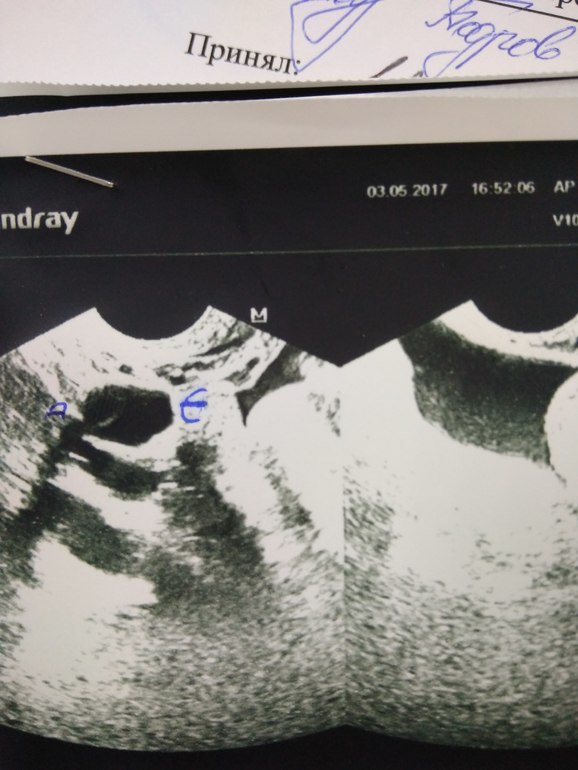

Посмотрите фото, это желтое тело?

ФолликулометрияВыкладывать фото с УЗИ,где мне поставили ЖТ 14мм, а сегодня оно исчезло. Девочки,кто разбирается, посмотрите опытным взглядом может врач ошиблась и это не ЖТ?